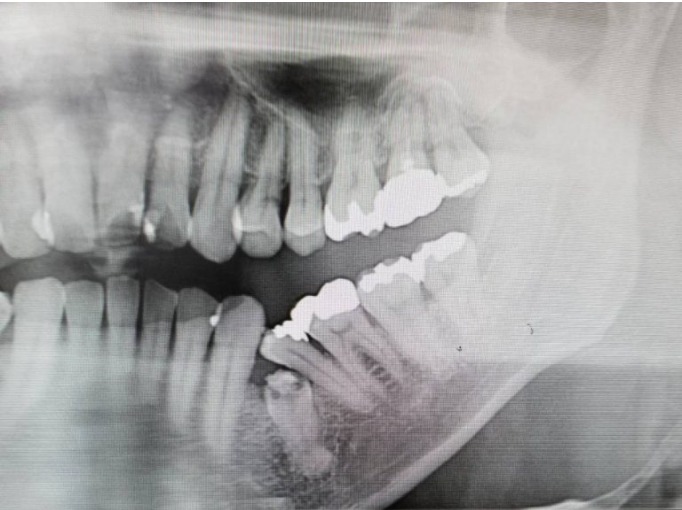

レントゲンでの埋伏歯

左下の「埋伏歯」の症例です。